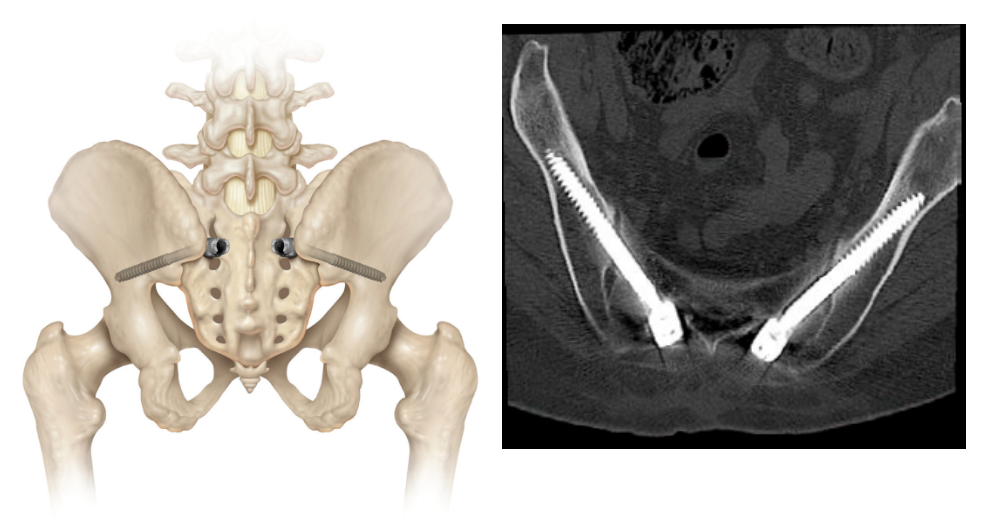

選擇合適直徑、長度的螺釘,使用上釘器對準(zhǔn)髂前上棘方向上釘

置入后透視確認(rèn)進(jìn)釘方向及位置

6. 置棒鎖緊

選擇合適長度的連接棒,棒可稍長避免末端滑脫。上棒前先將連接棒預(yù)彎,防止骶髂釘角度過大無法置棒

確認(rèn)合適后,鎖緊

德康S2AI骶髂釘?shù)呐R床應(yīng)用展示